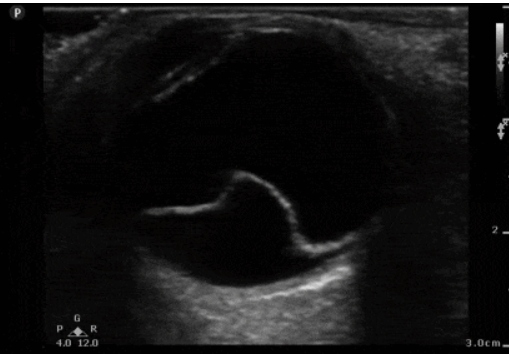

¿De qué zona es este corte? y ¿cuáles son las estrucutras que se ven?

Zona 1A

A - Tendón flexor digital superficial (TFDS)

B - Tendón flexor digital profundo (TFDP)

C - Ligamento frenador (Check Ligament)

D - Ligamento suspensorio del menudillo (LSM)